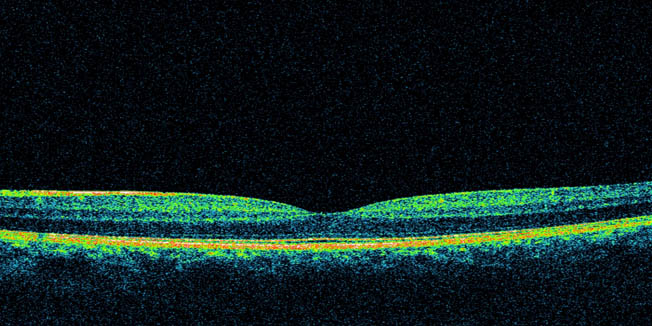

Snop laserske svjetlosti koji se odbija od očne pozadine nosi u sebi informaciju koja se može precizno prikazati ako taj snop interferira s referentnim snopom. Konačni rezultat te interferencije kompjutorski se obrađuje za svaku točku posebno i na kraju se slaže u sliku koja zapravo čini presjek očne pozadine. Ono što omogućuje ovu pretragu je i karakteristika same retine, a to je njezina prozirnost.

Današnji moderni OCT aparati omogućuju preciznije razlikovanje pojedinih slojeva mrežnice i može se reći da se sve više približavamo tome da ćemo imati nalaz identičan histološkom presjeku, a da nismo uzeli komadić tkiva.

U Klinici Svjetlost koristi se Spectral domain Optical Coherence Tomography – Copernicus, uređaj koji spada u najnoviju generaciju OCT uređaja. Uz pomoć softverskih alata omogućuje trodimenzionalni prikaz žute pjege te topografske prikaze na kojima se vide oscilacije u debljini mrežnice i njenih slojeva, pa do mogućnosti da se izolira pojedini sloj i zasebno analizira.